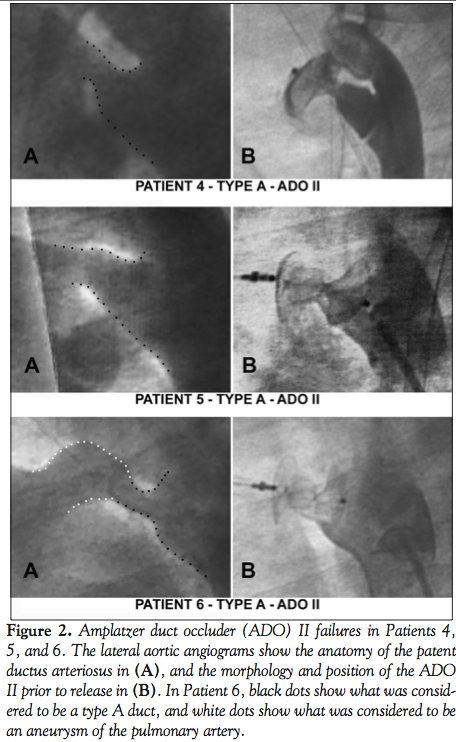

Failures (Table 2; Figures 1 and 2). Overall, there were 6 failures in 6 patients (4.3%): 3 recovered failures (2.1%), and 3 definite failures (2.1%). There were no failures in the coil group, 3 failures in the ADO I group (1 recovered), and 3 failures in the ADO II group (2 recovered).

For the ADO II, immediate closure was achieved in 73.8% of the cases (31/42 patients), rising to 95.2% (40/42 patients) at 24 hours, but decreasing again at 10 days to 92.8% (39/42) and remaining like that at 6 months. The ADO II device that failed secondarily at 10 days was in a 5-month-old, 6.6 kg baby girl, with a 3 mm type A PDA (Patient 4 in Table 2 and Figure 2). It was successfully closed with a 6-6 device with no residual shunt or aortic obstruction. However, the 10-day follow-up showed a residual shunt with severe aortic obstruction due

to a secondary kinking of the aortic retention disc (Figure 5). The device was surgically retrieved and the PDA ligated. There were also 2 recovered failures in the ADO II group (Patients 5 and 6 in Table 2 and Figure 2); a 2.5-year-old, 10 kg girl with a 4.6 mm type A PDA, and a 3-year-old, 23 kg boy with a 4.8 mm type A PDA. Both were initially closed with 6-6 ADO II, and both devices migrated to the left pulmonary artery, a few minutes following their detachment. The devices were immediately retrieved percutaneously in both patients. In the first patient, the duct was closed with a 12-10 ADO I during the same procedure. In the second patient, the duct was closed with a 10-8 ADO I 6 months later.

Other theoretical advantages of the ADO II may be incriminated in failures and act like double-edged swords. The symmetrical design of the device makes the arterial delivery more rapid and tempting, despite less control on the aortic disc. The multiple available sizes make it difficult to choose the correct size. A shorter device may lead to disc elongation and a loss in central disc diameter, thus causing a residual leak, or even dislodgment and migration. On the other hand, a longer device may lead to disc protrusion in either the aorta or pulmonary artery. Finally, malleability of the device may be linked to a higher rate of migration.12 In Patient 5 (10 kg, 4.6-mm wide, 11.5-mm long, type A PDA), we probably underestimated the duct diameter and didn’t take into account the cyclic variations (systole and diastole) which are significant in large ducts: a 30% variation for a 4.6 mm duct results in a diameter >5.5 mm, reaching the device’s superior limit. The ADO II migrated to the left pulmonary artery and was immediately retrieved. The duct was secondarily closed with an ADO I. In large, non-tubular ducts, and in short ones with a large aortic ampulla and fast tapering, the ADO I should probably be the first choice. The second ADO II migration occurred in a 23 kg patient with a very unusually shaped 19-mm long PDA (Figure 2; Patient 6); it had a large pulmonary ampulla, an uncommon tubular part, a 4.8 mm restriction, and then an aortic ampulla. The pulmonary ampulla was considered to be an aneurysm of the pulmonary artery and was excluded from the duct; hence, the rest of this duct could be classified as a classical type A PDA with fast tapering. With this strategic approach, the virtual reconstruction with a 6-6 ADO II seemed appropriate. Once again, the ADO II migrated to the left pulmonary artery a few minutes following its release. In this case, too, it was retrieved and the PDA was closed with an ADO I.